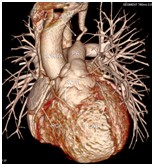

心脏大血管CT成像

冠状动脉CT成像